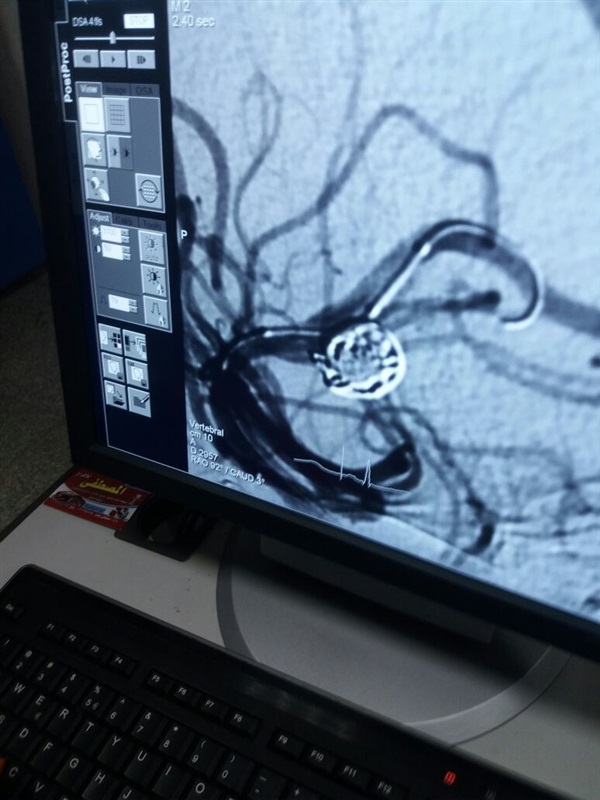

وأضاف الدكتور محمد عبد الله عباس رئيس قسم الأمراض النفسية والعصبية أن ورشة العمل بحضور الدكتور أحمد بسيوني أستاذ القسطرة المخية بجامعة عين شمس ومشاركة أعضاء هيئة التدريس ومعاونيهم والأطباء المقيمين بقسم الأمراض النفسية والعصبية بطب قنا والمستشفى الجامعي شهدت إجراء عمليات القسطرة المخية لأربعة حالات بواقع 2 حالة تشخيصية و 2 حالة علاجية حيث شهدت أحد الحالات لمريض يبلغ 60 عام تركيب عدد 2 دعامة حيث كان يعاني من ضيق في الشريان السباتي نتيجة لجلطات متكررة بالمخ كما شهدت حالة أخرى تبلغ 62 عام تركيب ملفات حلزونية لغلق التمدد الشرياني كما تم إجراء 2 قسطرة تشخيصية لمرضى يعانون من نزيف بالمخ وأوضح الدكتور محمد عبد الله عباس أن جميع الحالات تماثلت للشفاء من خلال متابعتها بالقسم الداخلي للقسم بمستشفى قنا الجامعي.